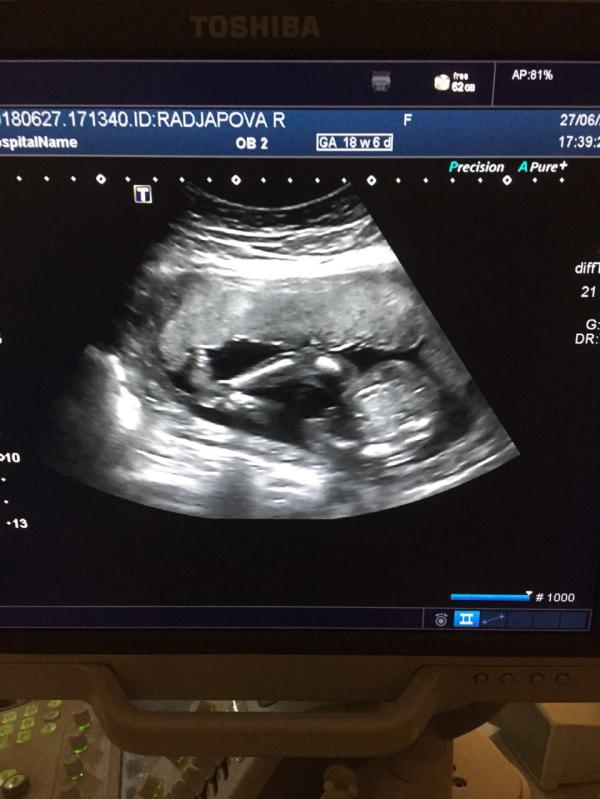

Прошли 2 скрининг) У нас будет мальчик) как назвать?)🤵💪